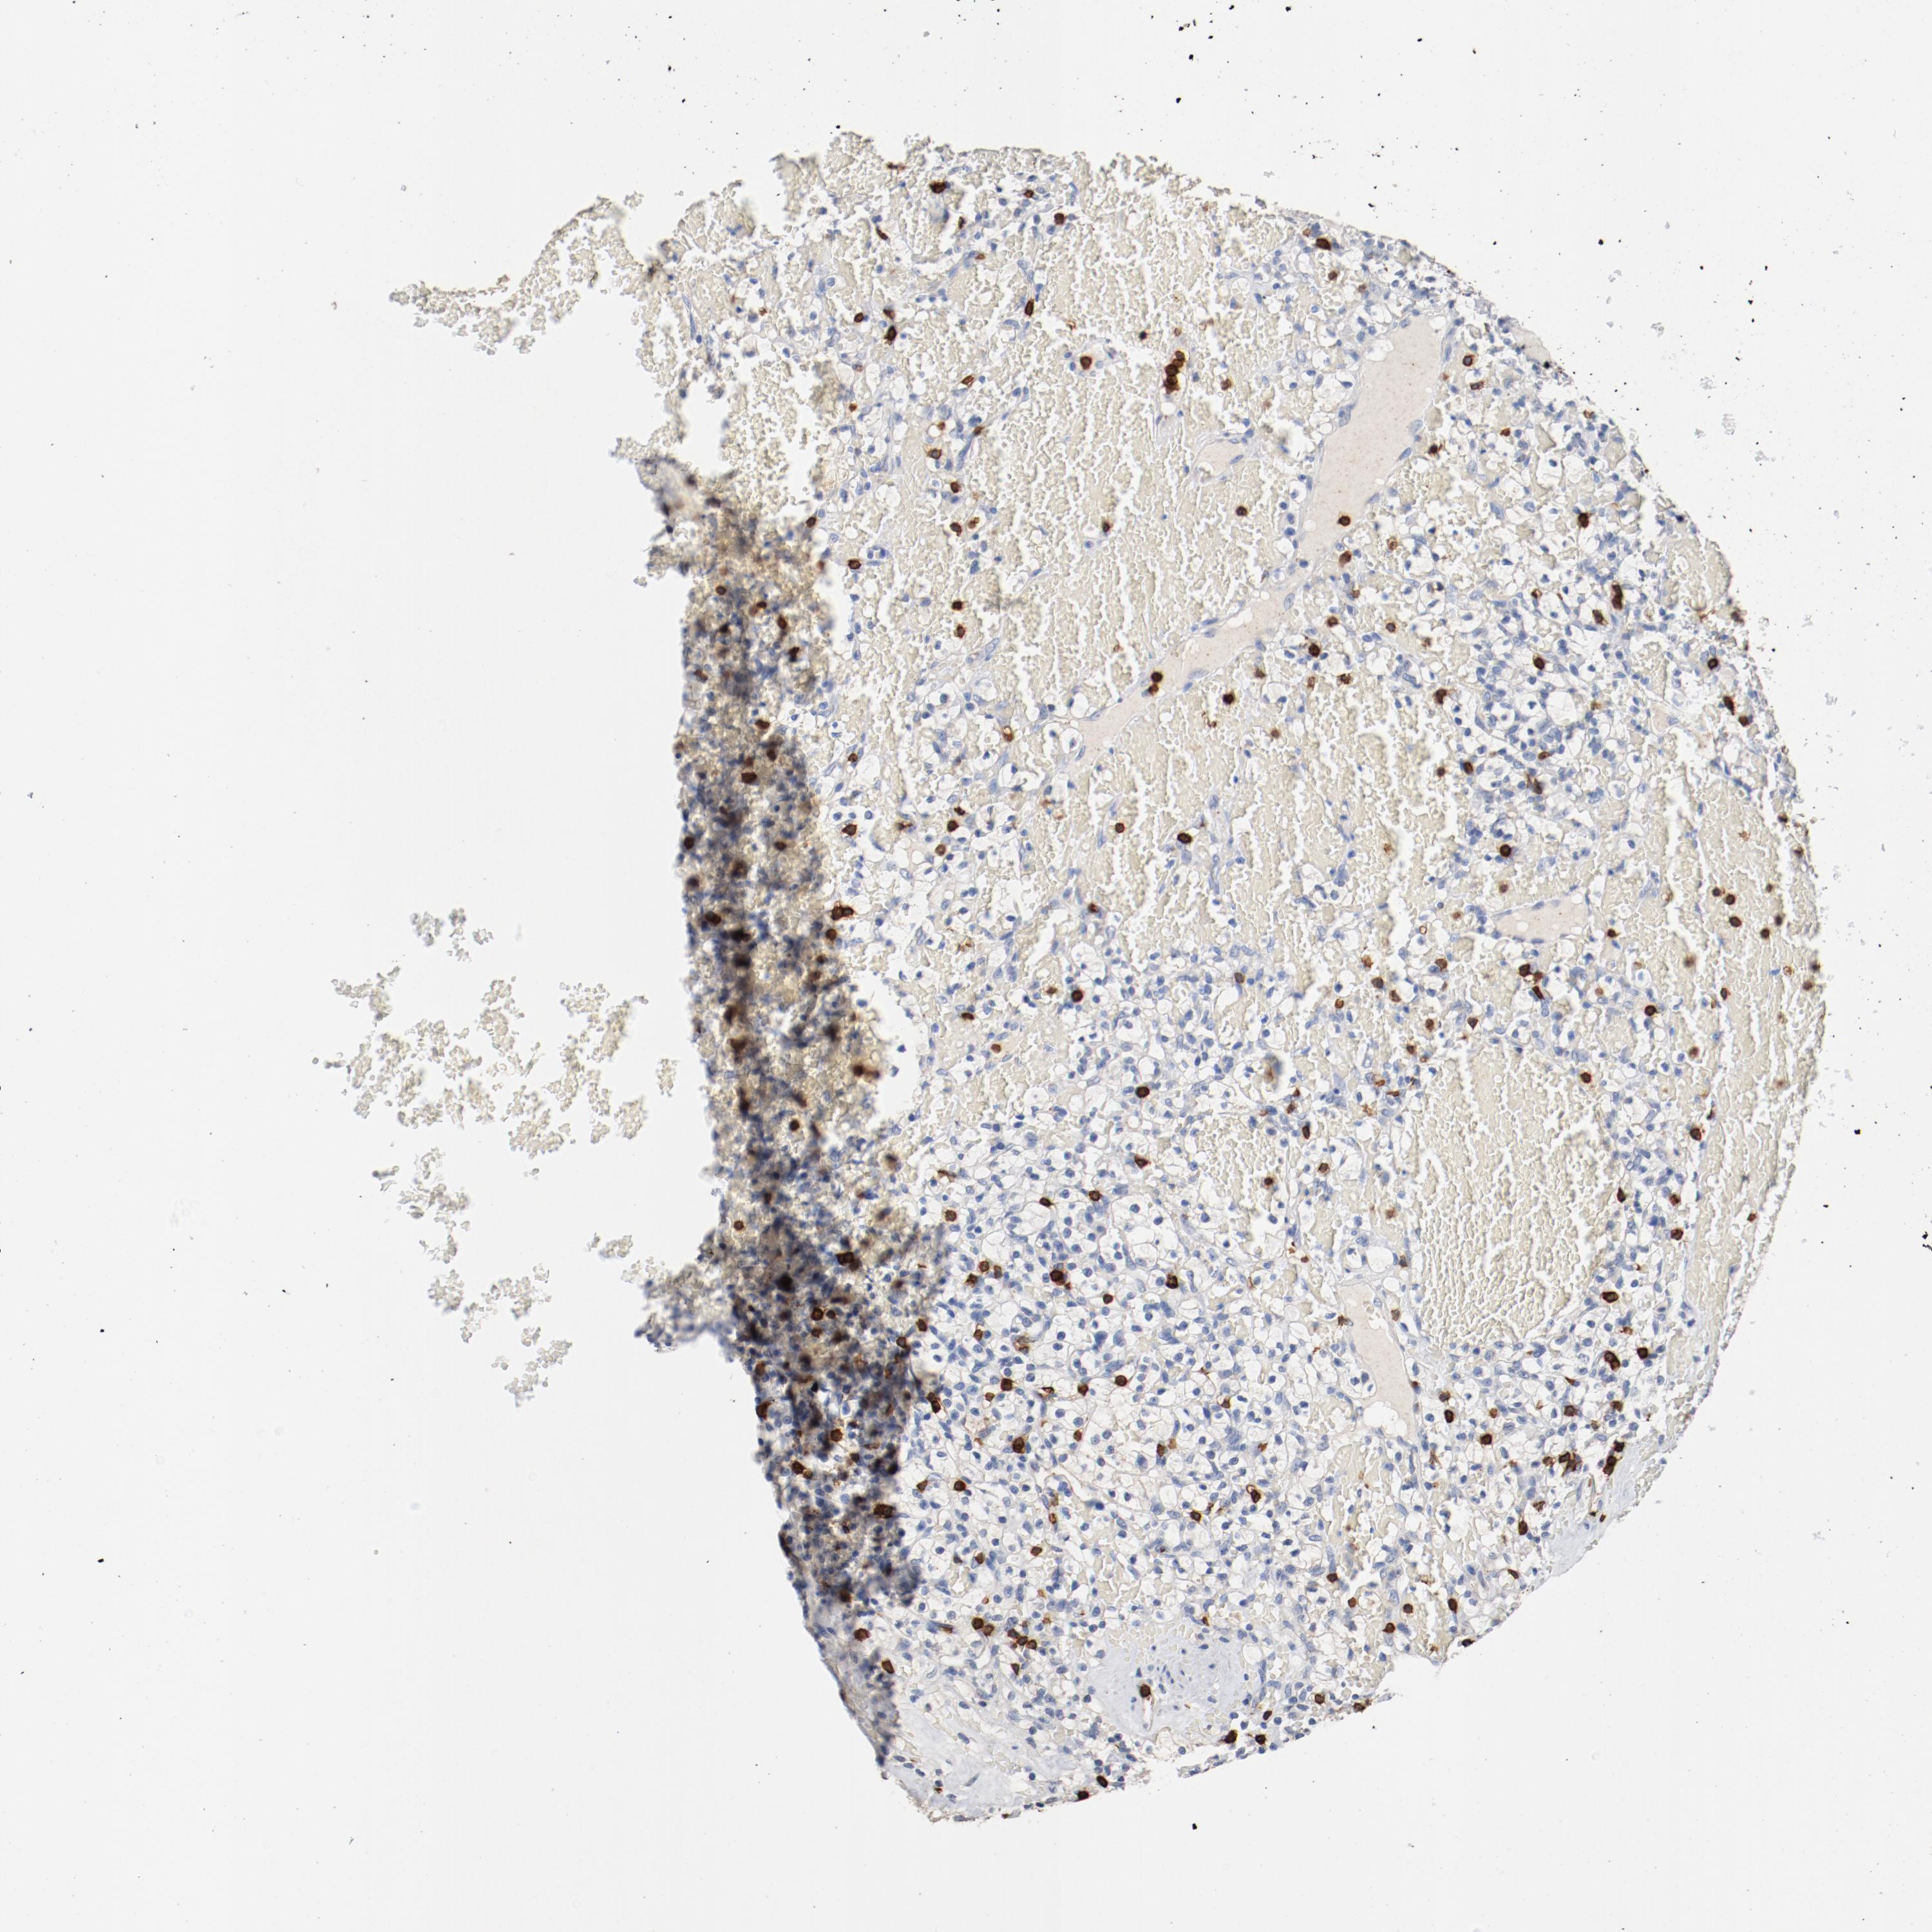

KIDNEY RENAL CLEAR CELL CARCINOMA (VALIDATION) - Interactive survival scatter ploti

The Survival Scatter plot shows the clinical status (i.e. dead or alive) for all individuals in the patient cohort, based on the same data that underlies the corresponding Kaplan-Meier plots. Patients that are alive at last time for follow-up are shown in blue and patients who have died during the study are shown in red.

The x-axis shows the expression levels (FPKM) of the investigated gene in the tumor tissue at the time of diagnosis. The y-axis shows the follow-up time after diagnosis (years). Both axes are complimented with kernel density curves demonstrating the data density over the axes. The top density plot shows the expression levels (FPKM) distribution among dead (red) and alive patients (blue). The right density plot shows the data density of the survived years of dead patients with high and low expression levels respectively, stratified using the cutoff indicated by the vertical dashed line through the Survival Scatter plot. This cutoff is automatically defined based on the FPKM cutoff that minimizes the p-score. The cutoff can be changed by dragging the vertical line or by entering a cutoff value in the square labeled "Current cut-off".

Under the Survival Scatter plot the p-score landscape (black curve; left axis) is shown together with dead median separation (red curve; right axis). Dead median separation is the difference in median mRNA expression between patients who have died with high and low expression, respectively. It is calculated as follows: median FPKM expression of dead patients with high expression - median FPKM expression of dead patients with low expression. This is intended to aid the user in visually exploring custom cutoffs and the associated p-scores and dead median separation.

Individual patient data is displayed and can be filtered by clicking on one or more of the category buttons on the top of the page. Categories describing expression level and patient information include: high, low, alive, dead, female, male and tumor stages. The scale of the x-axis can be toggled between linear and log-scale by clicking on the "x log" button. Mouse-over function shows TCGA ID, patient information and mRNA expression (FPKM) for each patient.

& Survival analysisi

Kaplan-Meier plots summarize results from analysis of correlation between mRNA expression level and patient survival. Patients were divided based on level of expression into one of the two groups "low" (under cut off) or "high" (over cut off). X-axis shows time for survival (years) and y-axis shows the probability of survival, where 1.0 corresponds to 100 percent.

CD247 is not prognostic in Kidney Renal Clear Cell Carcinoma (validation)

Best expression cut offi

Based on the FPKM value of each gene, patients were classified into two groups and association between prognosis (survival) and gene expression (FPKM) was examined. The best expression cut-off refers the FPKM value that yields maximal difference with regard to survival between the two groups at the lowest log-rank P-value. Best expression cut-off was selected based on survival analysis .

When clicking on this number, the vertical dashed line indicating cut-off, the interactive survival plot, and the Kaplan-Meier curve will be adjusted to show results based on the best expression cut-off.

: 14.81

P scorei

Log-rank P value for Kaplan-Meier plot showing results from analysis of correlation between mRNA expression level and patient survival.

N/A

TCGA RNA samplesi

RNA-seq data is reported as average FPKM (number Fragments Per Kilobase of exon per Million reads), generated by the The Cancer Genome Atlas (TCGA) .

Normal distribution across the dataset is visualized with box plots, shown as median and 25th and 75th percentiles. Points are displayed as outliers if they are above or below 1.5 times the interquartile range. FPKM values of the individual samples are presented next to the box plot.

Average pTPM 11.7

Number of samples 100